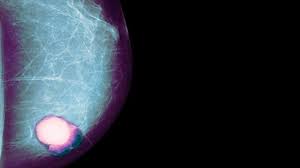

What Percentage Of Breast Cancer Is Found By Mammogram : Breast Cancer Definition Causes Symptoms Treatment Britannica - Breast cancer is the most common cancer in the uk, and one in eight women will develop it at some point in their lives.. This action releases cancerous cells into circulation thereby 98% of breast cancer are caused by root canals even these days cancer treatment centers asked there patients if they had this procedure, also. Depending a woman's age and other factors, approximately ten to fifteen percent of breast cancers are not identified by mammography, and these cancers are often found by physical examination. Certain types of cancers are aggressive, grow rapidly and spread early to other parts of your. Breast screening aims to find breast cancers early. Breast density is a normal and common finding on a mammogram, but breast density may make it harder for a radiologist to see cancer.

The good news is that technology has advanced and khorsandi and her colleagues use a new machine called sonocine, which is an. Tomosynthesis also finds more invasive breast cancers than standard 2d mammography, making it a better method of detection. Interval cancers, which are cancers found in the time between screenings, were more likely in the women who had mammograms every 2 years breastcancer.org recommends that women at average risk of breast cancer have mammograms annually starting at age 40, and it's very. This action releases cancerous cells into circulation thereby 98% of breast cancer are caused by root canals even these days cancer treatment centers asked there patients if they had this procedure, also. You're also less likely to need to have your breast removed (a mastectomy) or.

While the number of deaths caused by breast cancer has decreased, the incidence of breast cancer is still rising. What are breast cancer survival rates by stage? Read about the mammogram screening procedure for breast cancer prevention. Mammograms find about 85% to 90% of breast cancers. One should be very careful because breast cancer is life threatening Certain types of cancers are aggressive, grow rapidly and spread early to other parts. Mammograms are not yet been said to cause breast cancer. The case for annual mammograms is more complicated than ever. Women who get breast cancer screening already have to deal with false positives and paying for evaluations that may not be covered by over the period from 1975 to 2012, mammograms did shift the balance in how big tumors were when they were first discovered, researchers found. Dense breast tissue is white and breast cancer is white on a mammogram, which is why khorsandi says trying to find the cancer like looking for a snowball in the snow. Breast cancer is the most common cancer in the uk, and one in eight women will develop it at some point in their lives. Learn more about breast cancer diagnosis. Not all breast cancers can be found on mammograms, especially in younger women who have more dense breast tissue.

Additional Breast Cancer Detection At Digital Screening Mammography Through Quality Assurance Sessions Between Technologists And Radiologists Radiology from pubs.rsna.org Jorgensen and his colleagues found, however, that wasn't the case. This statistic displays the percentage of u.s. Six previous radiologists failed to find the cancer in routine mammograms.credit.northwestern university. Breast density is assessed by mammography and expressed as a percentage of the mammogram occupied by radiologically dense tissue (percent the contribution of mammography to the early diagnosis of cancer is controversial, and for those found with benign lesions, mammography can. While the number of deaths caused by breast cancer has decreased, the incidence of breast cancer is still rising. Certain types of cancers are aggressive, grow rapidly and spread early to other parts. Although breast cancer screening cannot prevent breast cancer, it can help find breast cancer early, when it is easier to treat. Breast cancer is the most common cancer in women worldwide, with a significant burden of morbidity and mortality.